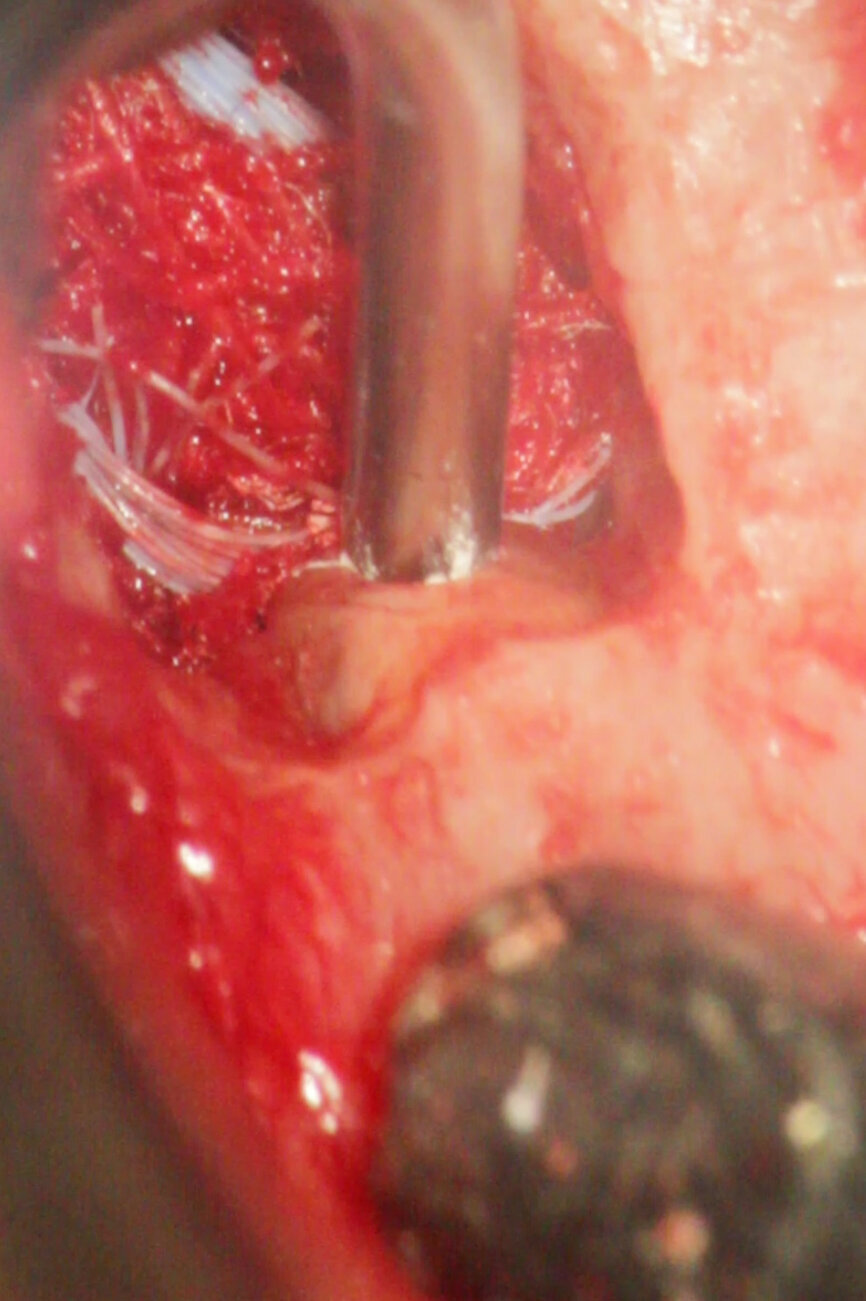

Fig. 4a: (a) Pre-op radiograph with a large periradicular lesion. (b) Periapical surgery. (c) MTA application with the MAP System and PD MTA White. (d) Condensation of the MTA with pluggers. (e) Mirror view of the root-end cavity filled with MTA. (f) Post-op radiograph showing the root-end filling.

Fig. 4b: (a) Pre-op radiograph with a large periradicular lesion. (b) Periapical surgery. (c) MTA application with the MAP System and PD MTA White. (d) Condensation of the MTA with pluggers. (e) Mirror view of the root-end cavity filled with MTA. (f) Post-op radiograph showing the root-end filling.

Fig. 4c: (a) Pre-op radiograph with a large periradicular lesion. (b) Periapical surgery. (c) MTA application with the MAP System and PD MTA White. (d) Condensation of the MTA with pluggers. (e) Mirror view of the root-end cavity filled with MTA. (f) Post-op radiograph showing the root-end filling.

Fig. 4d: (a) Pre-op radiograph with a large periradicular lesion. (b) Periapical surgery. (c) MTA application with the MAP System and PD MTA White. (d) Condensation of the MTA with pluggers. (e) Mirror view of the root-end cavity filled with MTA. (f) Post-op radiograph showing the root-end filling.

Fig. 4e: (a) Pre-op radiograph with a large periradicular lesion. (b) Periapical surgery. (c) MTA application with the MAP System and PD MTA White. (d) Condensation of the MTA with pluggers. (e) Mirror view of the root-end cavity filled with MTA. (f) Post-op radiograph showing the root-end filling.

Fig. 4f: (a) Pre-op radiograph with a large periradicular lesion. (b) Periapical surgery. (c) MTA application with the MAP System and PD MTA White. (d) Condensation of the MTA with pluggers. (e) Mirror view of the root-end cavity filled with MTA. (f) Post-op radiograph showing the root-end filling.

MTA is the material with the most favourable outcome as a root-end filling material for apical surgery. MTA has been associated with significantly less inflammation, cementum formation over MTA and regeneration of the periradicular tissue (Figs. 4a–f).[2]